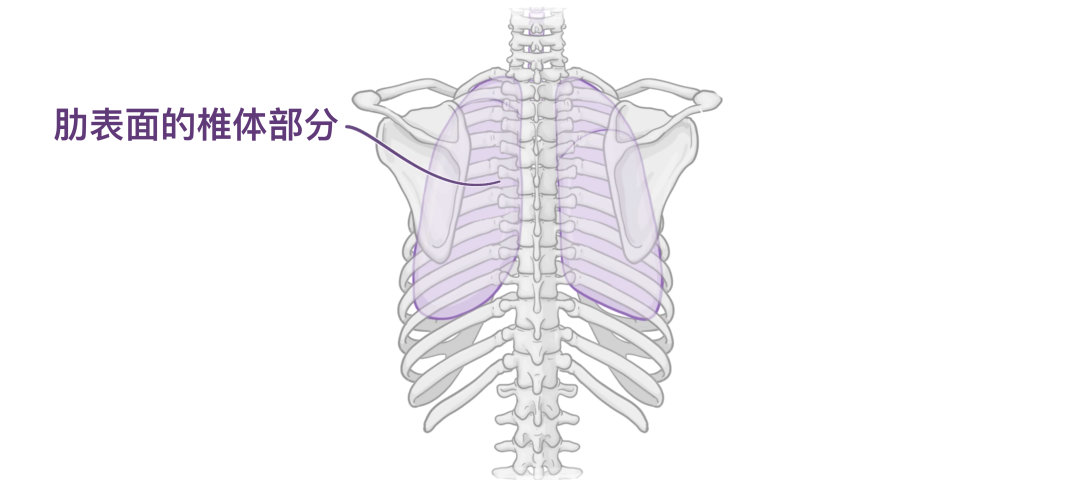

接下来是肺表面。双肺的肋面大、光滑且凸出,与肋 胸膜相关,肋胸膜将其与肋骨、肋软骨和肋间肌分开。

肋面的后部与胸椎体相关,有时称为肋面的椎骨部分。